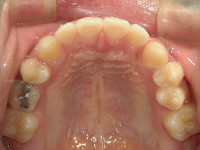

顎顔面矯正治療では、急速拡大装置という特殊な装置を使って、歯だけでなく顎の骨自体を矯正していきます。

顎の骨が広がれば、歯は正しい位置へ自然に収まり、歯並びも美しくなります。

~顎顔面矯正治療で骨格から美しい歯並びに~